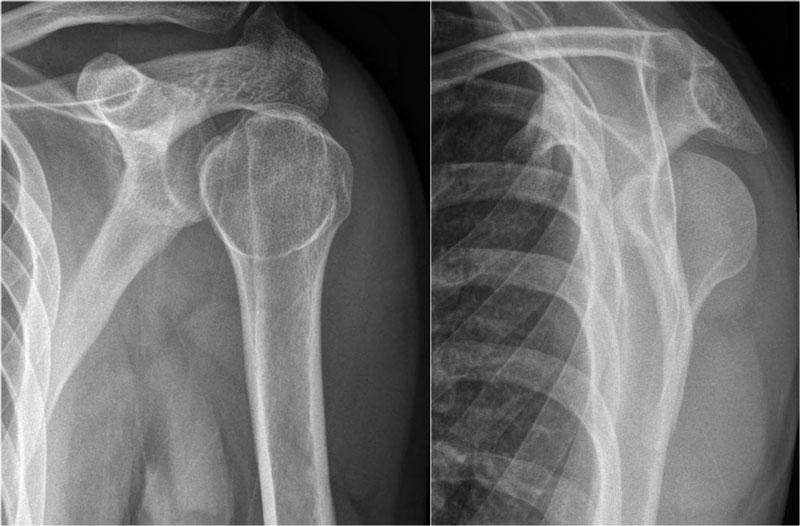

Trật khớp ra sau

Trật khớp ra sau ít gặp và dễ bị bỏ sót, do mức độ di lệch ít hơn so với trật khớp ra trước.

Trên phim thẳng (AP), chỏm xương trông bất thường do xoay trong.

Trên phim chếch qua xương bả vai (transscapular-Y), chỏm xương cánh tay bị di lệch ra sau.

Đôi khi mức độ di lệch khó đánh giá, đặc biệt khi phim chếch qua xương bả vai bị xoay nhẹ.

Đôi khi phim chụp tư thế nách có thể hữu ích, nhưng khi còn nghi ngờ nên chỉ định chụp CT.

Cuộn qua các hình ảnh.

Hình ảnh của một bệnh nhân khác bị trật khớp ra sau.

Lưu ý khoảng cách giữa chỏm xương cánh tay và ổ chảo trên phim thẳng (AP) rộng bất thường.

Trật khớp vai ra sau ít gặp và không rõ ràng trên phim X-quang như trật khớp ra trước.

Khoảng một nửa số trường hợp trật khớp vai ra sau không được chẩn đoán ngay lần khám đầu tiên, do mức độ nghi ngờ lâm sàng thấp và hình ảnh học chưa đầy đủ.

Trật khớp ra sau chiếm 2-4% tổng số các trường hợp trật khớp vai.

Trật khớp ra sau có liên quan đến cơn động kinh, chấn thương năng lượng cao, điện giật và liệu pháp sốc điện.

Trên các hình ảnh, quan sát thấy trật khớp ra sau kèm gãy xương.